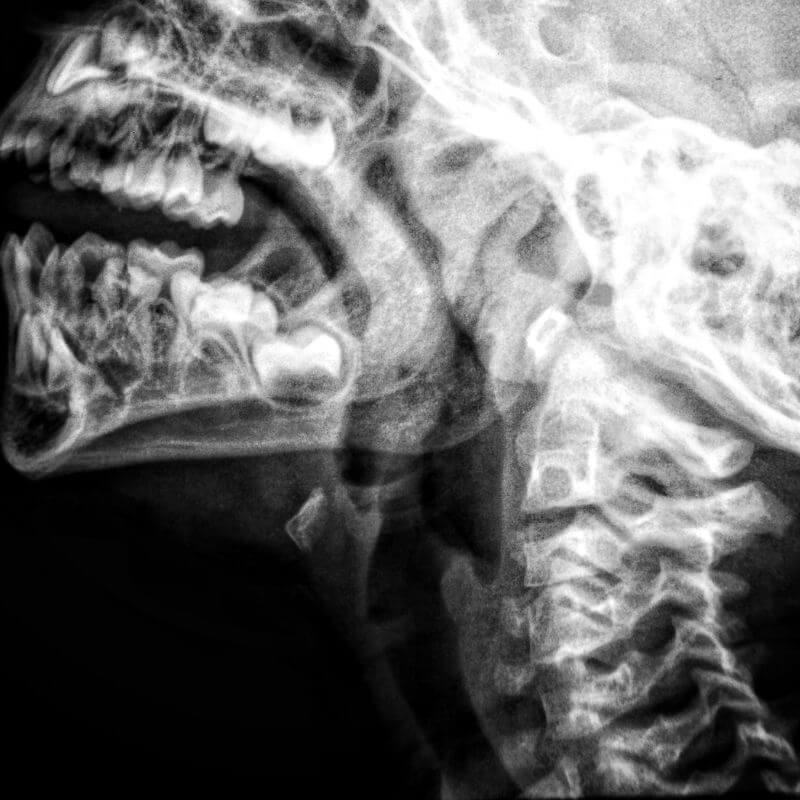

Los rayos X son un tipo de radiación electromagnética similar a la luz visible. Sin embargo, a diferencia de la luz, estos rayos tienen mayor